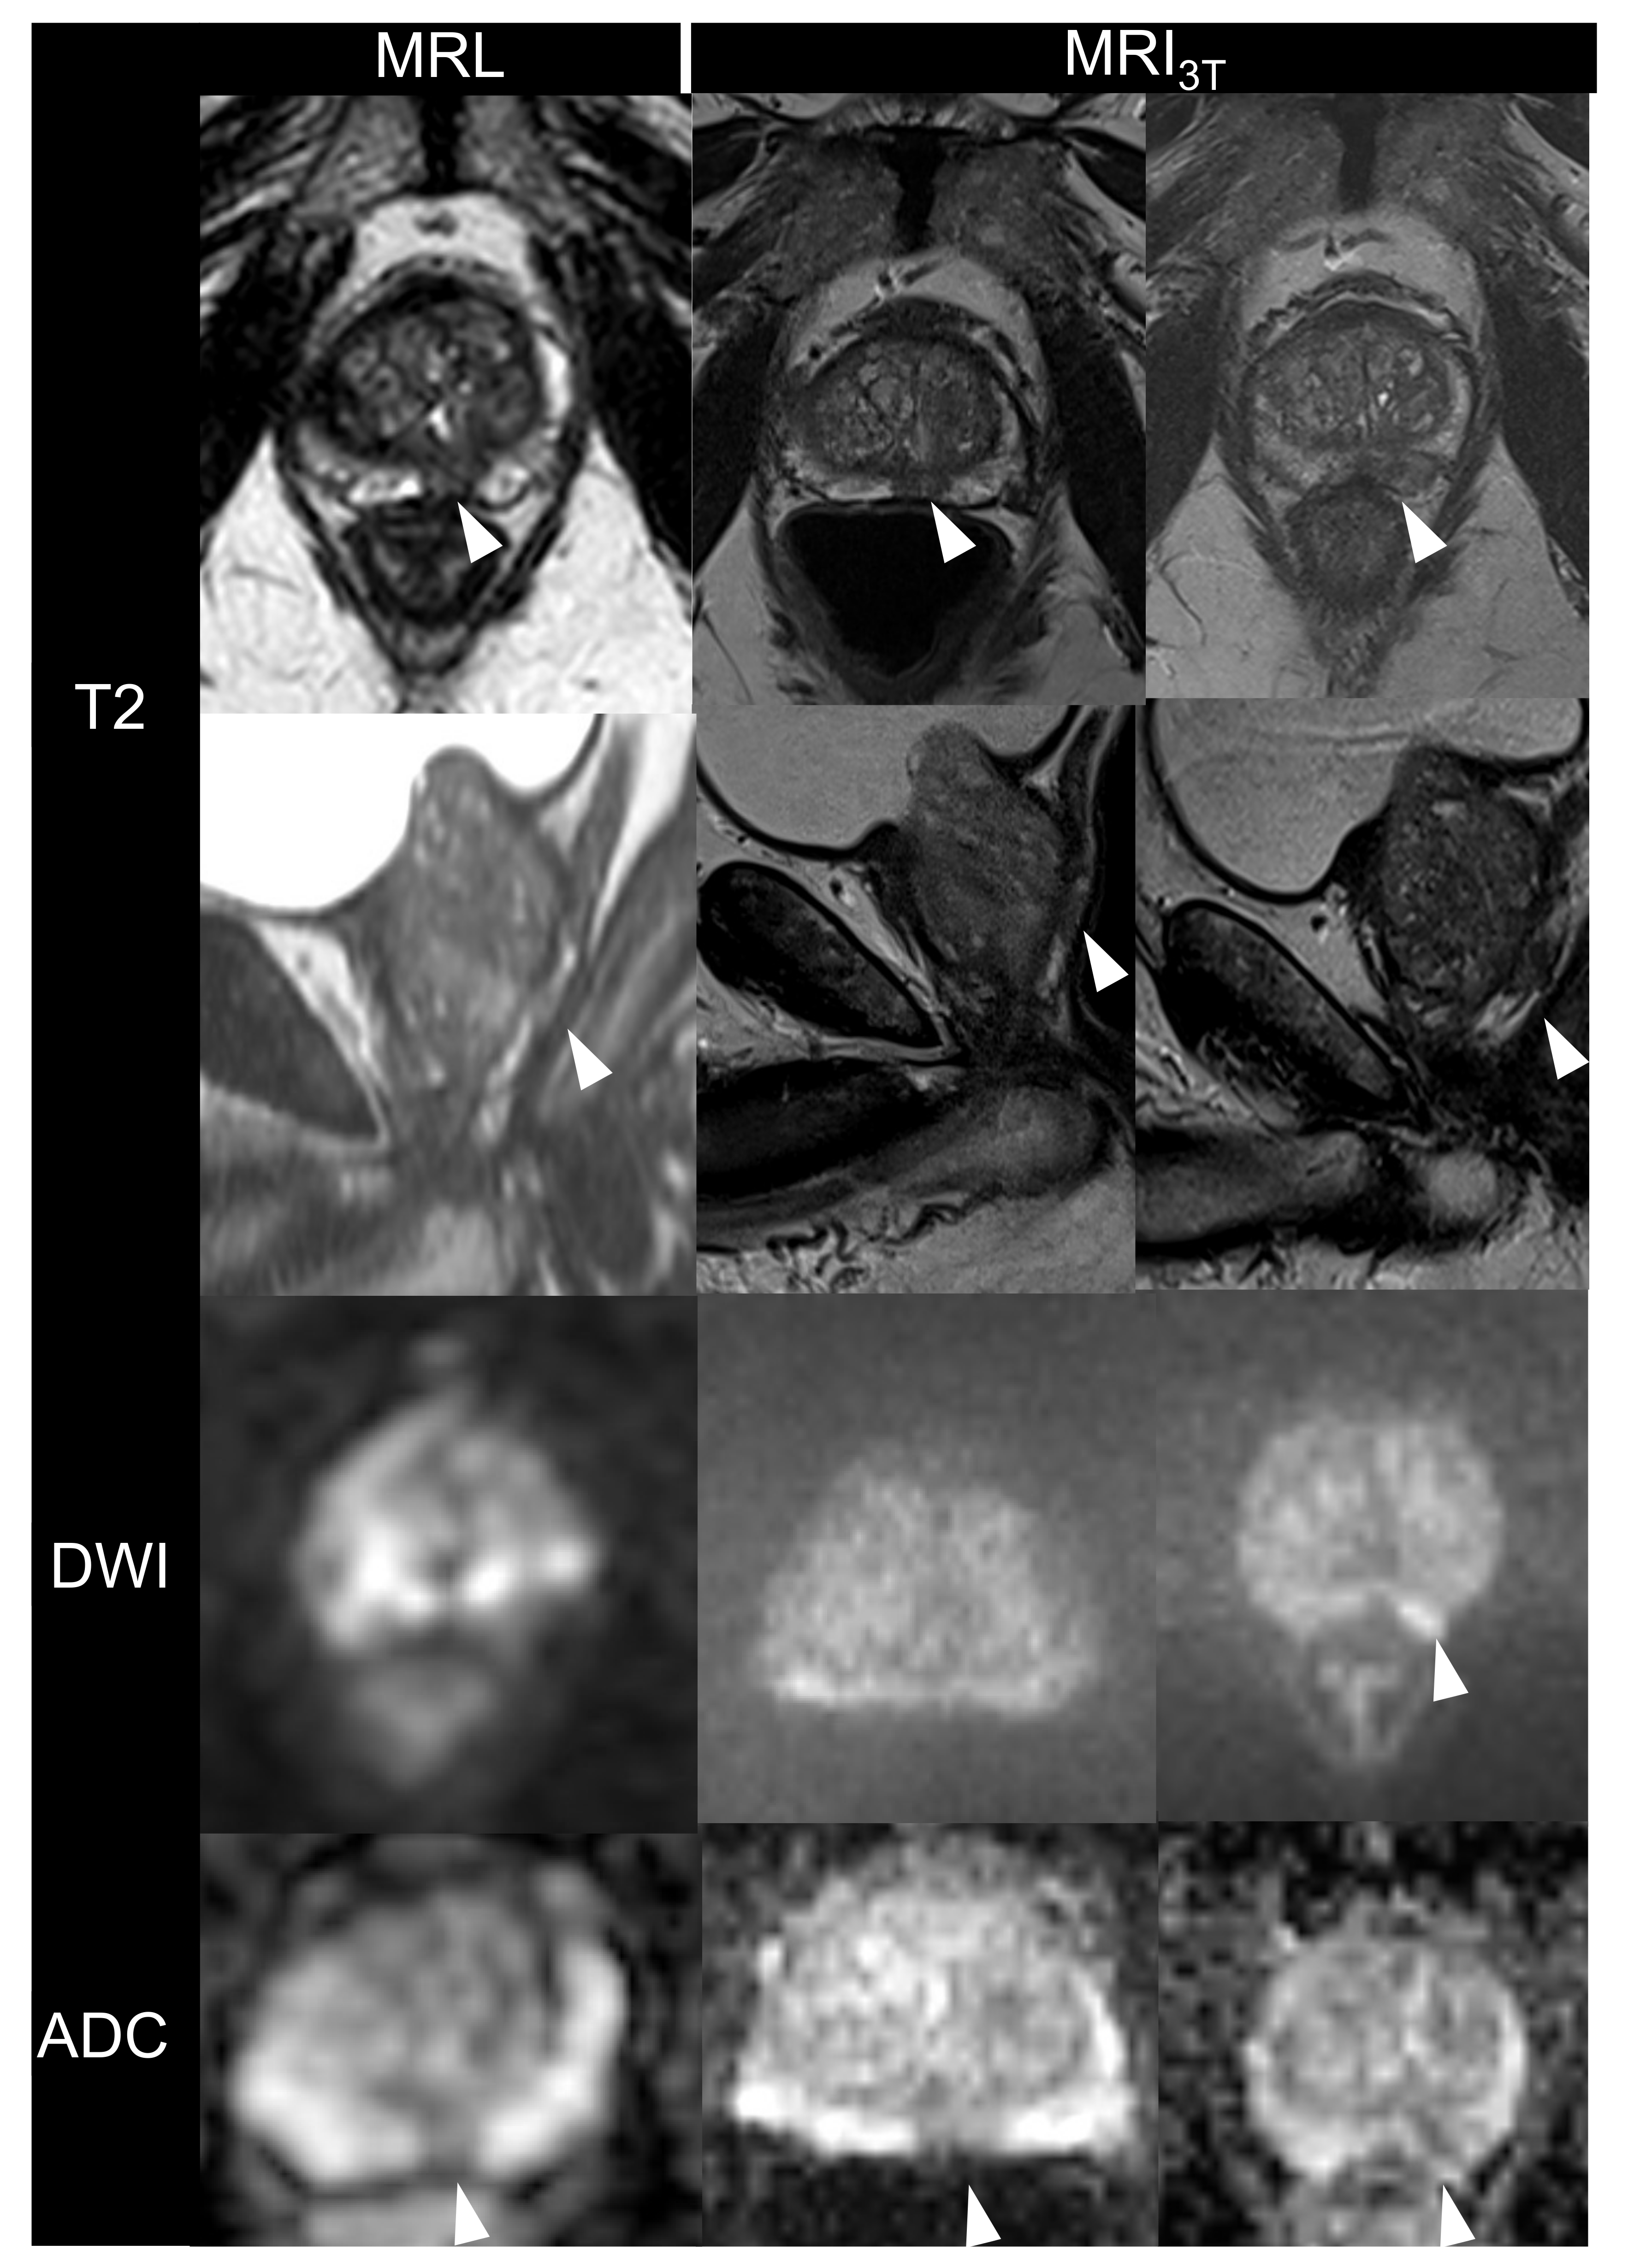

3.1.1. Image Quality

3.1.2. Lesion Conspicuity and Diagnostic Confidence on MRL Alone and in Consensus with MRI3T